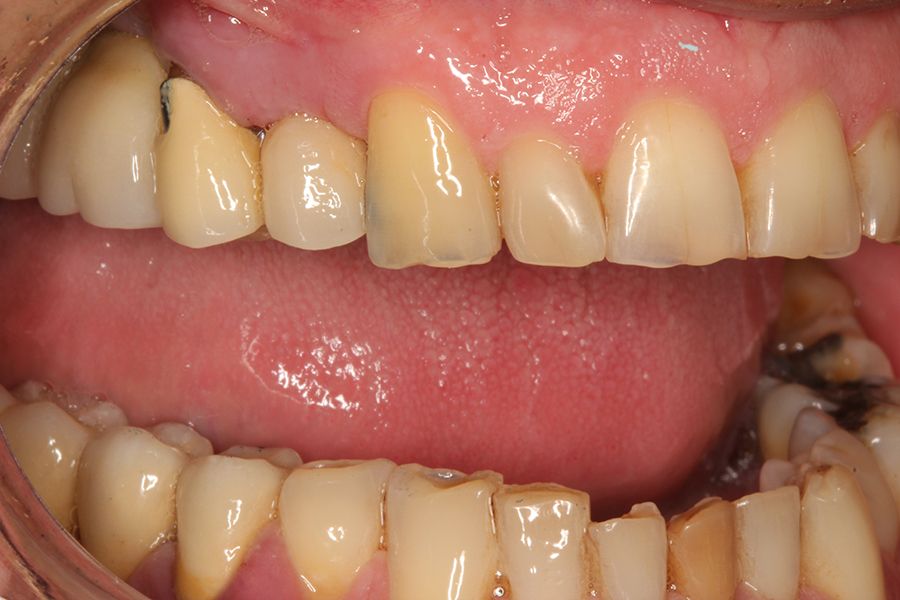

En las figuras 5-13 se muestra uno de los casos incluidos en el estudio.

En todos los pacientes se identificaron eventos adversos en sus rehabilitaciones con implantes, siendo estas complicaciones: fractura de la cerámica de la prótesis en un 63,6%, fractura estructural de la prótesis en un 18,2% de los casos (estructura en sí misma o recubrimiento de resina en las híbridas) y fracturas o fisuras en los implantes en un 18,2% de los casos. Las fracturas de las prótesis y de los implantes se vieron por igual entre hombres y mujeres, siendo la fractura de cerámica algo mayor en el grupo de los hombres (figura 1).